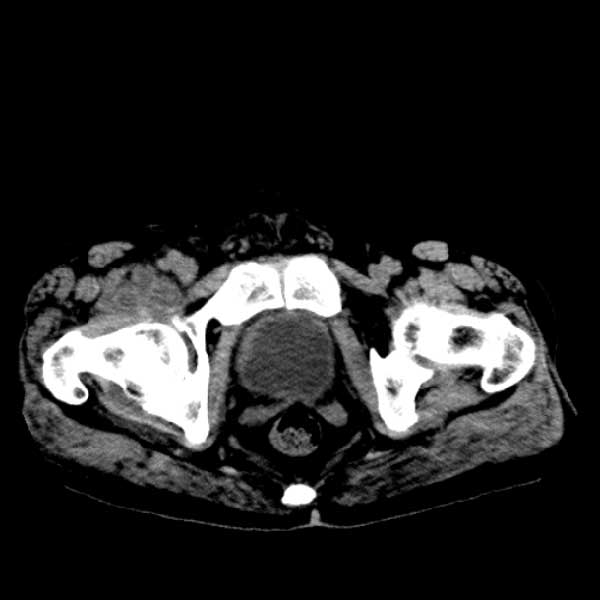

标题: CT13513:男 71 腹部疼痛20余天,近几天高热就诊,骨窗未见异 [打印本页]

标题: CT13513:男 71 腹部疼痛20余天,近几天高热就诊,骨窗未见异

考虑感染性病变可能性大,起源于阑尾?

感染,脓肿形成

考虑为化脓性阑尾炎.脓肿形成.及多肌肉累及.

考虑右侧腰大肌脓肿,向右髂窝、右腹股沟流注。

支持化脓性阑尾炎伴右髂窝脓肿、腰大肌腰方肌脓肿形成。

考虑腹腔及盆腔化脓性炎症,累及右侧髋关节及腹股沟区.

首先考虑化脓性阑尾炎伴腰大肌、腰方肌脓肿,不除外回盲部结核。

回盲部癌待排除。

患者肠镜检查考虑结肠癌,病理证实

患者肠镜检查考虑结肠癌,病理证实。肺部ct可见多发结节,考虑转移